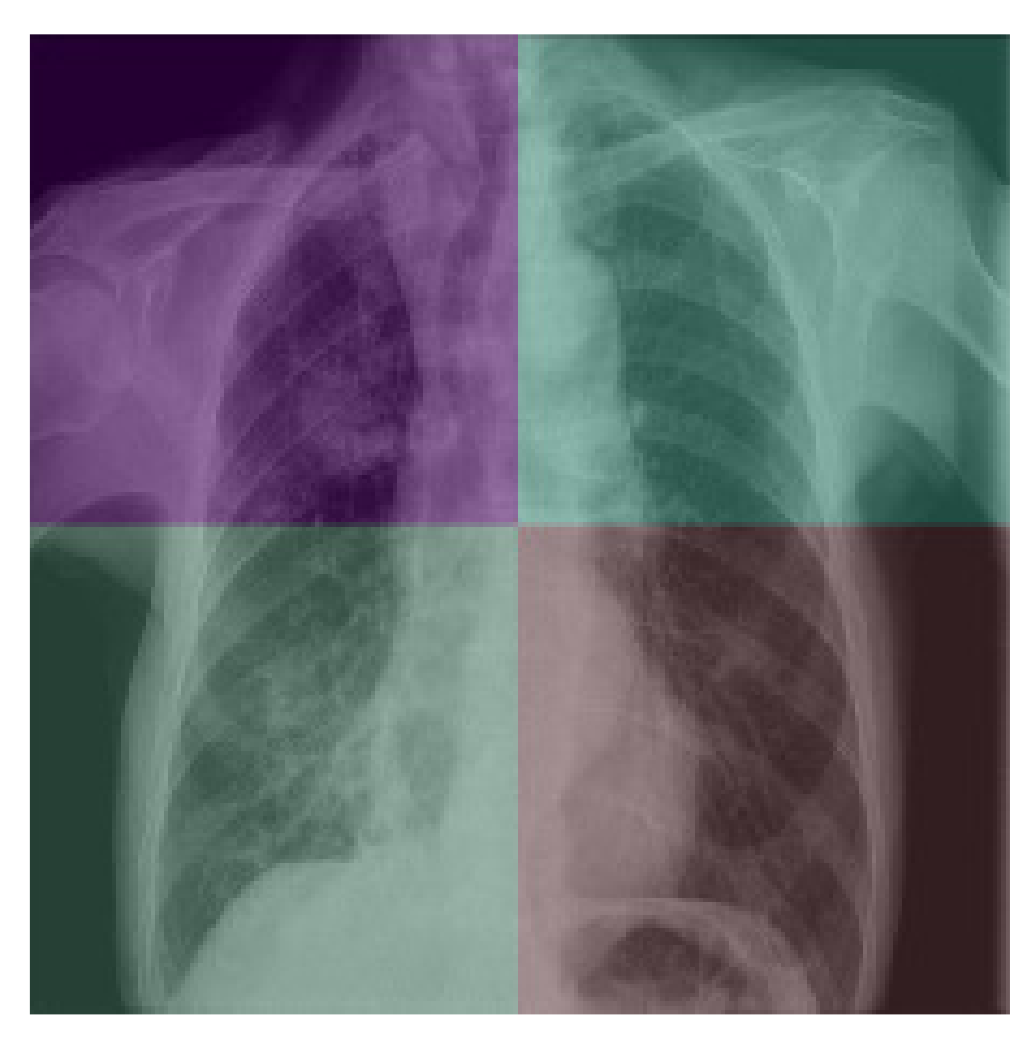

The next category of data augmentation we used involved adding noise, applying a median filter, conducting image inpainting, and adjusting brightness. These were all attempts to lower image quality and add artifacts that simulate defects found in real world scans. For noise, we randomly generated Gaussian noise and added it to the image. For larger speckle noise, we generated the same Gaussian noise but then used a median filter to bunch the noise up into dot-like artifacts on the image. For image inpainting, we first generated noise and used it as a mask, deleting the parts of the image where noise was present. We then used inpainting to take into account the nearest pixels to fill in the now empty areas where the noise mask was on the image. Finally, for brightness, we used the inbuilt Keras ImageDataGenerator class to randomly adjust the brightness of the image. These data augmentation techniques all served to prepare the model for more realistic scenarios where the X-ray may not be as clean as in a database. An example of a image quality augmentation can be seen in Figure 5.

Figure 5.

Image Quality augmentation on X-ray from [8].